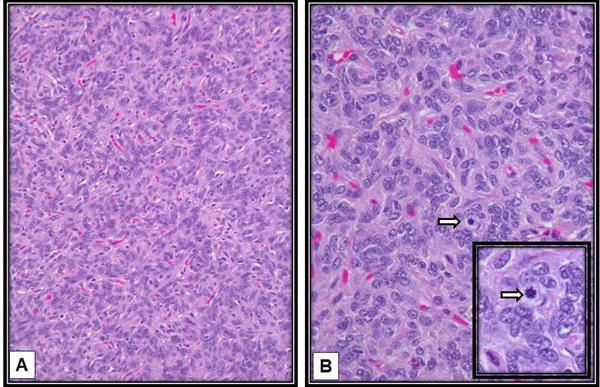

Histopathological examination revealed a lesion composed of oval to spindle shaped cells with focal haemangiopericytoma like vasculature [Table/Fig-6]. Tumour cells showed patternless arrangement. Extracellular collagen deposition was seen focally. Few cells showed intranuclear inclusion body. Few multinucleate giant cells were also observed. Necrosis was not seen. Mitosis was 3-4 /10 High Power Fields (HPF) in highest proliferating areas. On immunohistochemistry, the tumour cells showed CD34, Bcl-2 and MIC-2 positivity. It was seen to be negative for CD31, EMA and PR [Table/Fig-7]. The tumour was concluded to be a solitary fibrous tumour with atypical features. However, it did not show any malignant features.

Histopathology. Slide A shows oval to spindle shaped cells with focal haemangiopericytomatous vasculature. The tumour cells show patternless arrangement (H&E stain,100X). Slide B shows a mitotic figure (arrow) in highest proliferating area; inset shows magnified view of the mitotic figure. (H&E stain,400X).